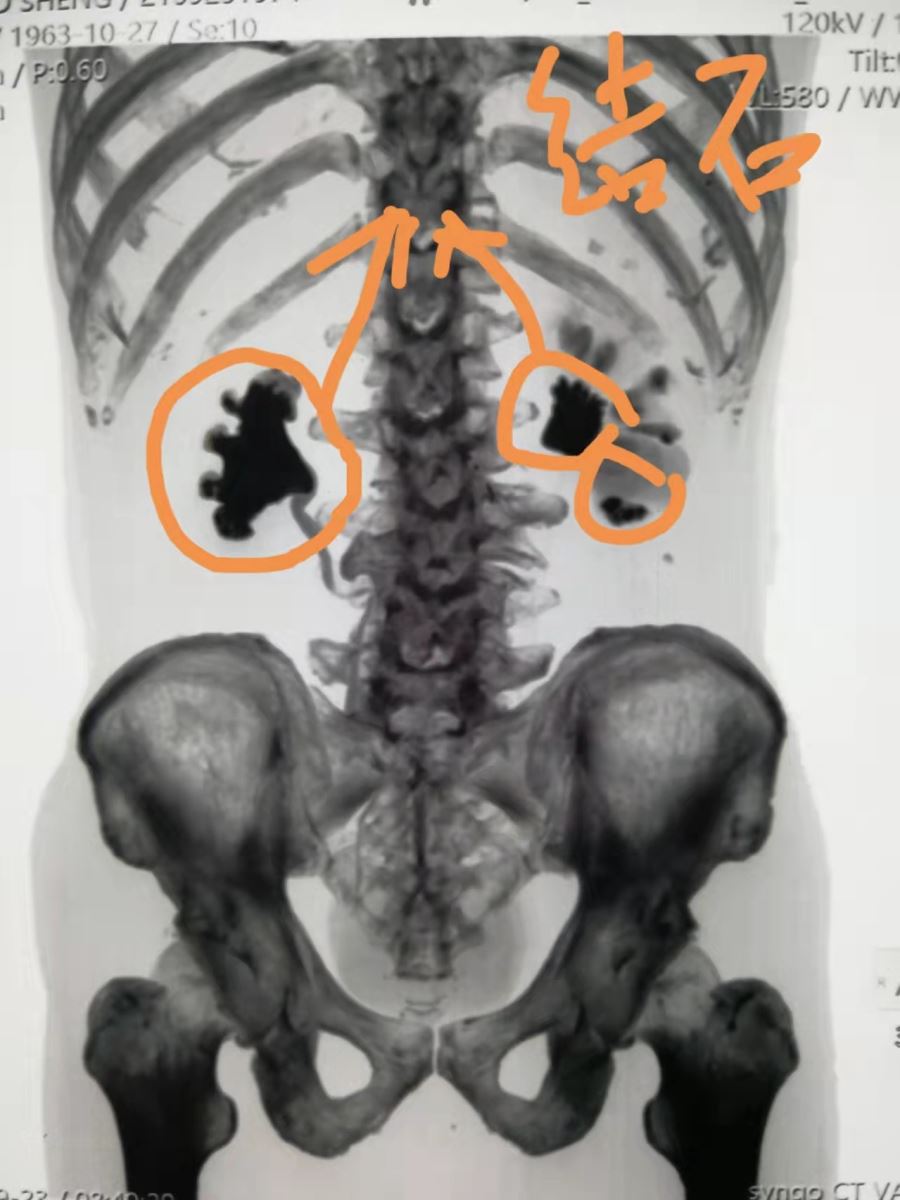

近日,我院泌尿外科徐志强主任医师与团队,为一名巨大右肾铸形结石、左肾多发结石的患者成功实施“经皮肾镜钬激光碎石取石术”。

患者杨某,男,58岁,入院40天前经彩超检查发现巨大右肾铸形结石、左肾多发结石。曾前往市内、外多家医院就诊,因结石过于巨大和复杂,均未接诊,此次慕名来我院泌尿外科求治。经完善检查,充分术前准备,先期处理了肾积水较为严重的左肾多发结石,两周后为右肾实施手术,手术历时2个小时十分钟,顺利取出粉末化的结石,复查无明显结石残留。目前,患者在泌尿外科医护人员的精心呵护下已经痊愈出院。

术前影像